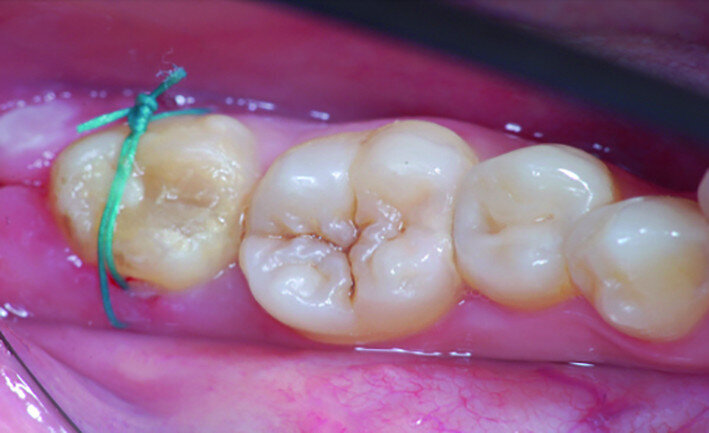

Fig. 8: Transplanted tooth sutured, immediately after surgery.

After local anaesthesia with 2 per cent mepivacaine with 1:100,000 adrenaline, the right maxillary second molar was atraumatically extracted. Initially with a size 15c surgical blade, the periotomy was realised and then the tooth was extracted after separating the roots to avoid unnecessary trauma to the alveolar bone. Then the donor right maxillary third molar was extracted after periotomy as described and transplanted into the adjacent site. Because of the slight differences in the root anatomy, it was necessary to remove the intraradicular bone septum of the receiving site to al- low tooth positioning, and a odontoplastic of the donor tooth crown was performed to maintain it not in occlusion. An antibiotic (amoxicillin/clavulanic acid, 1 g, by mouth twice a day for five days) was prescribed, along with rinses with 0.2 per cent chlorhexidine. The tooth was keep stable with sutures (Fig. 8). A periapical radiograph was taken (Fig. 9). At the suture removal at two weeks, the tooth showed good stability, and positive adaptation of the soft tissue was observed (Fig. 10). At four weeks, the tooth was stable and the soft tissue looked healthy (Fig. 11). The patient did not show any adverse effects and stated that the tooth was fully functional. Examination of the avulsed second molar showed the extent of the perforation (Figs. 12 & 13).